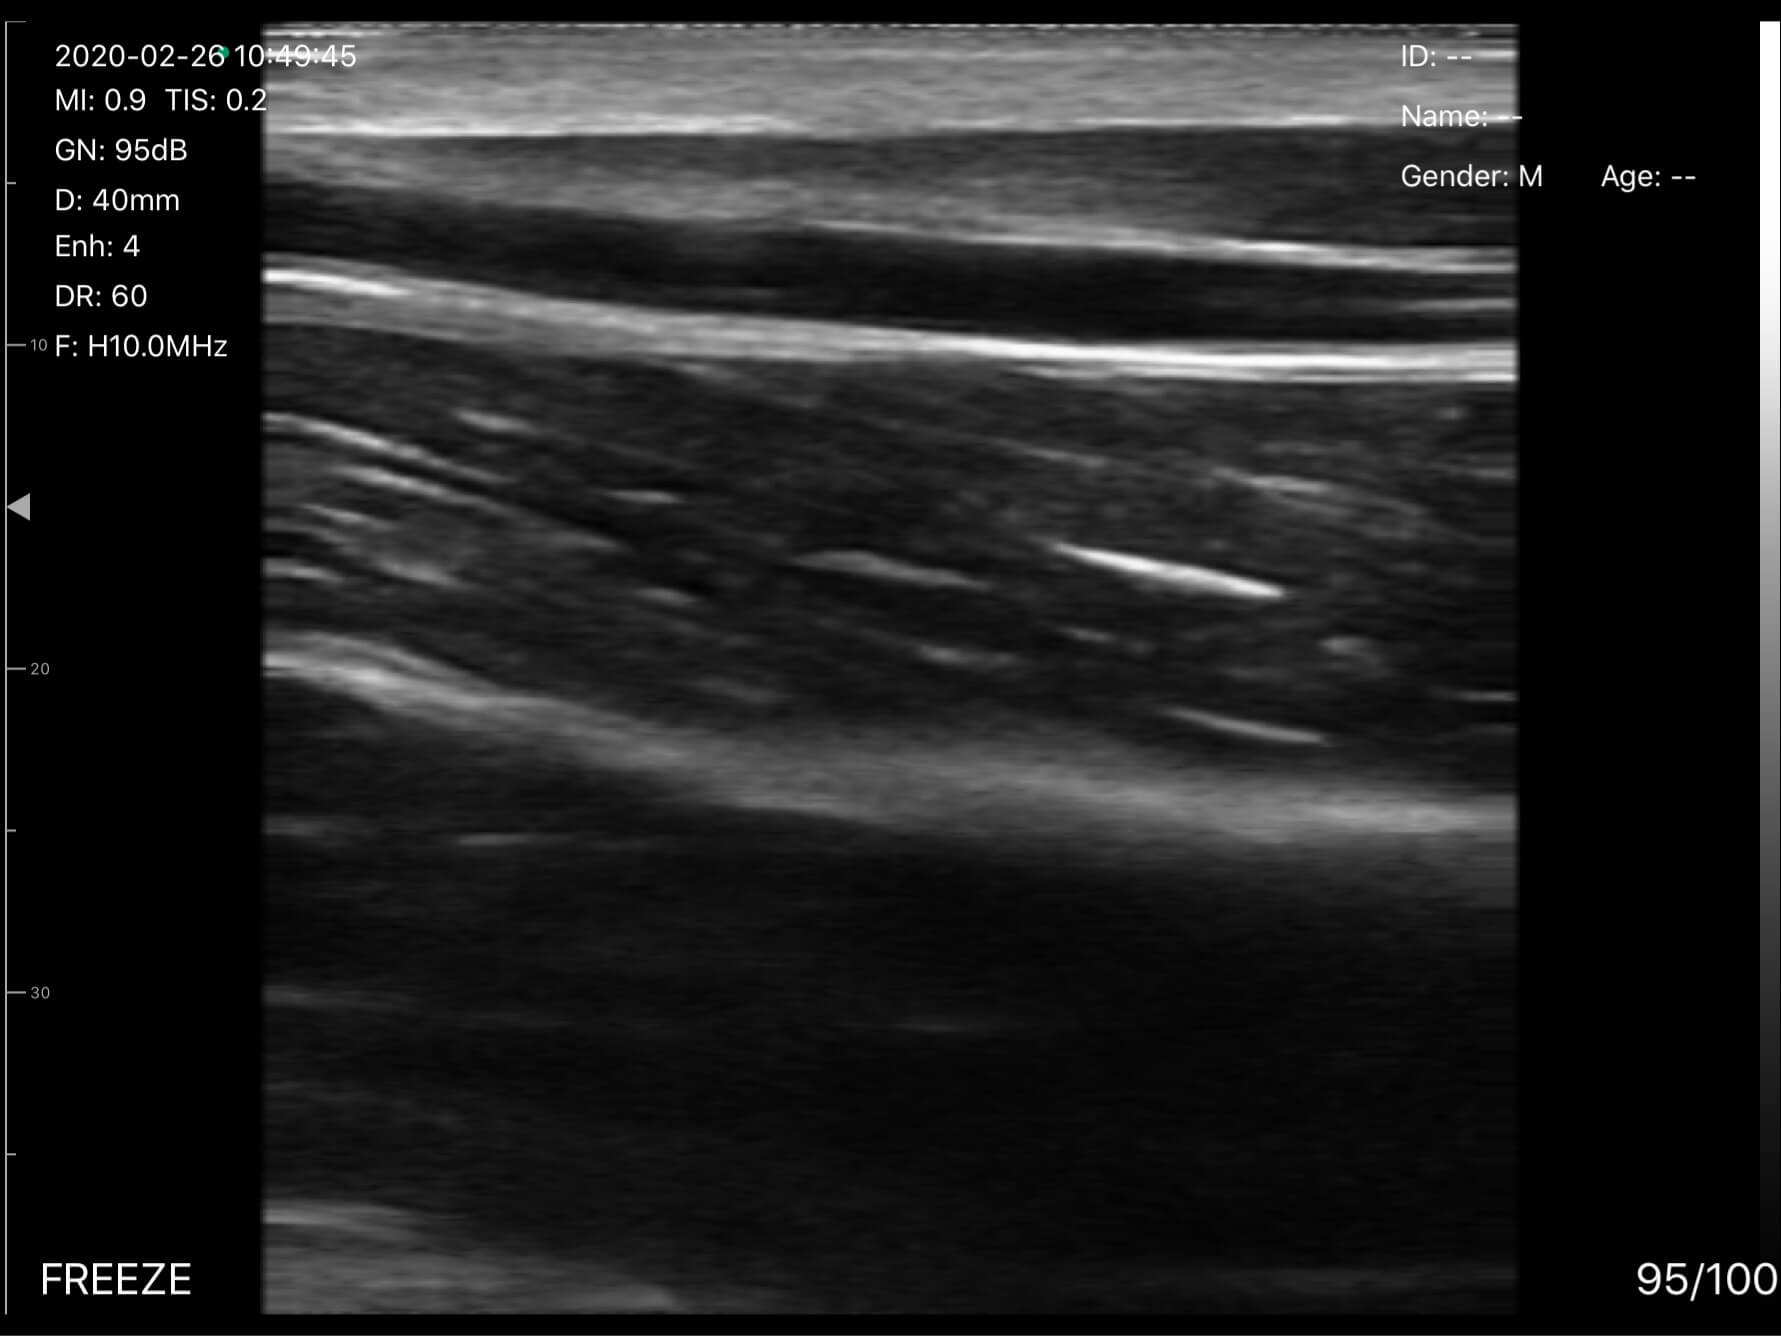

EagleView Uprobe-L uses up to 10MHz linear high-frequency linear array to produce high resolution images of structures near the body surface. Perfect for vascular imaging, also for MSK, breast, thyroid, carotid and certain procedures such as placing intravenous (IV) lines, central venous catheters, or for ultrasound-guided vascular access in emergency and critical care settings.

Visualizing Blood Vessels, Veins, and Arteries

Vascular imaging with B,M modes, allows healthcare professionals to assess vascular structures, and observe the movement of vessel walls in real-time.

Carotide

Poignet Vaisseau